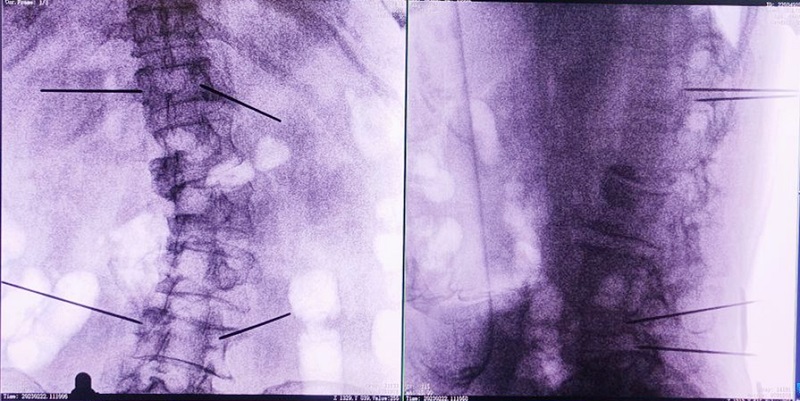

(3)根據(jù)設(shè)定好的的位置和入針?lè)较?,植入引?dǎo)針;

(4)所有引導(dǎo)針植入完畢后,沿引導(dǎo)針?lè)较蜻M(jìn)行椎弓根及椎體置管,建立通道;